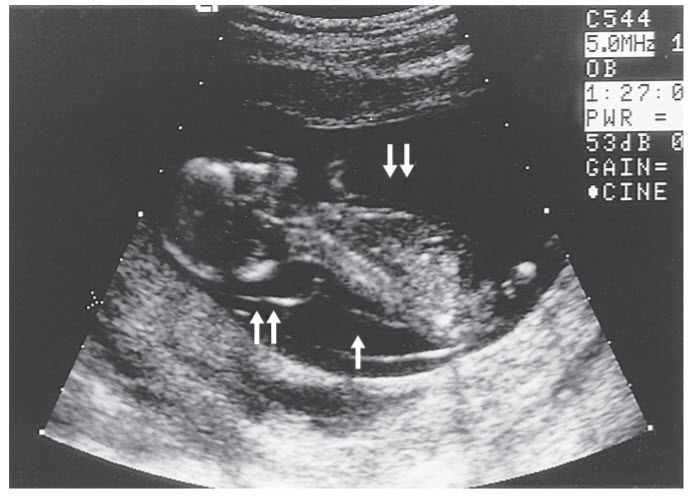

The sonographic image shows a 13-week-old fetus with a large NT (double arrows) and early hydrops, sometimes called a cystic hygroma. In the second and third trimesters, cystic hygromas are commonly associated with Turner syndrome (45, X). In early pregnancy, however, 50% of cases will be associated with a trisomy, usually trisomy 21, trisomy 18, or trisomy 13. Of those cases that are chromosomally normal, most of these nuchal translucencies disappear, and the fetus goes on to have perfectly normal development.